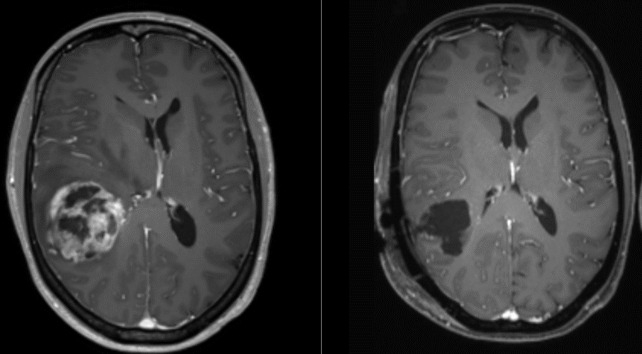

glioblastome